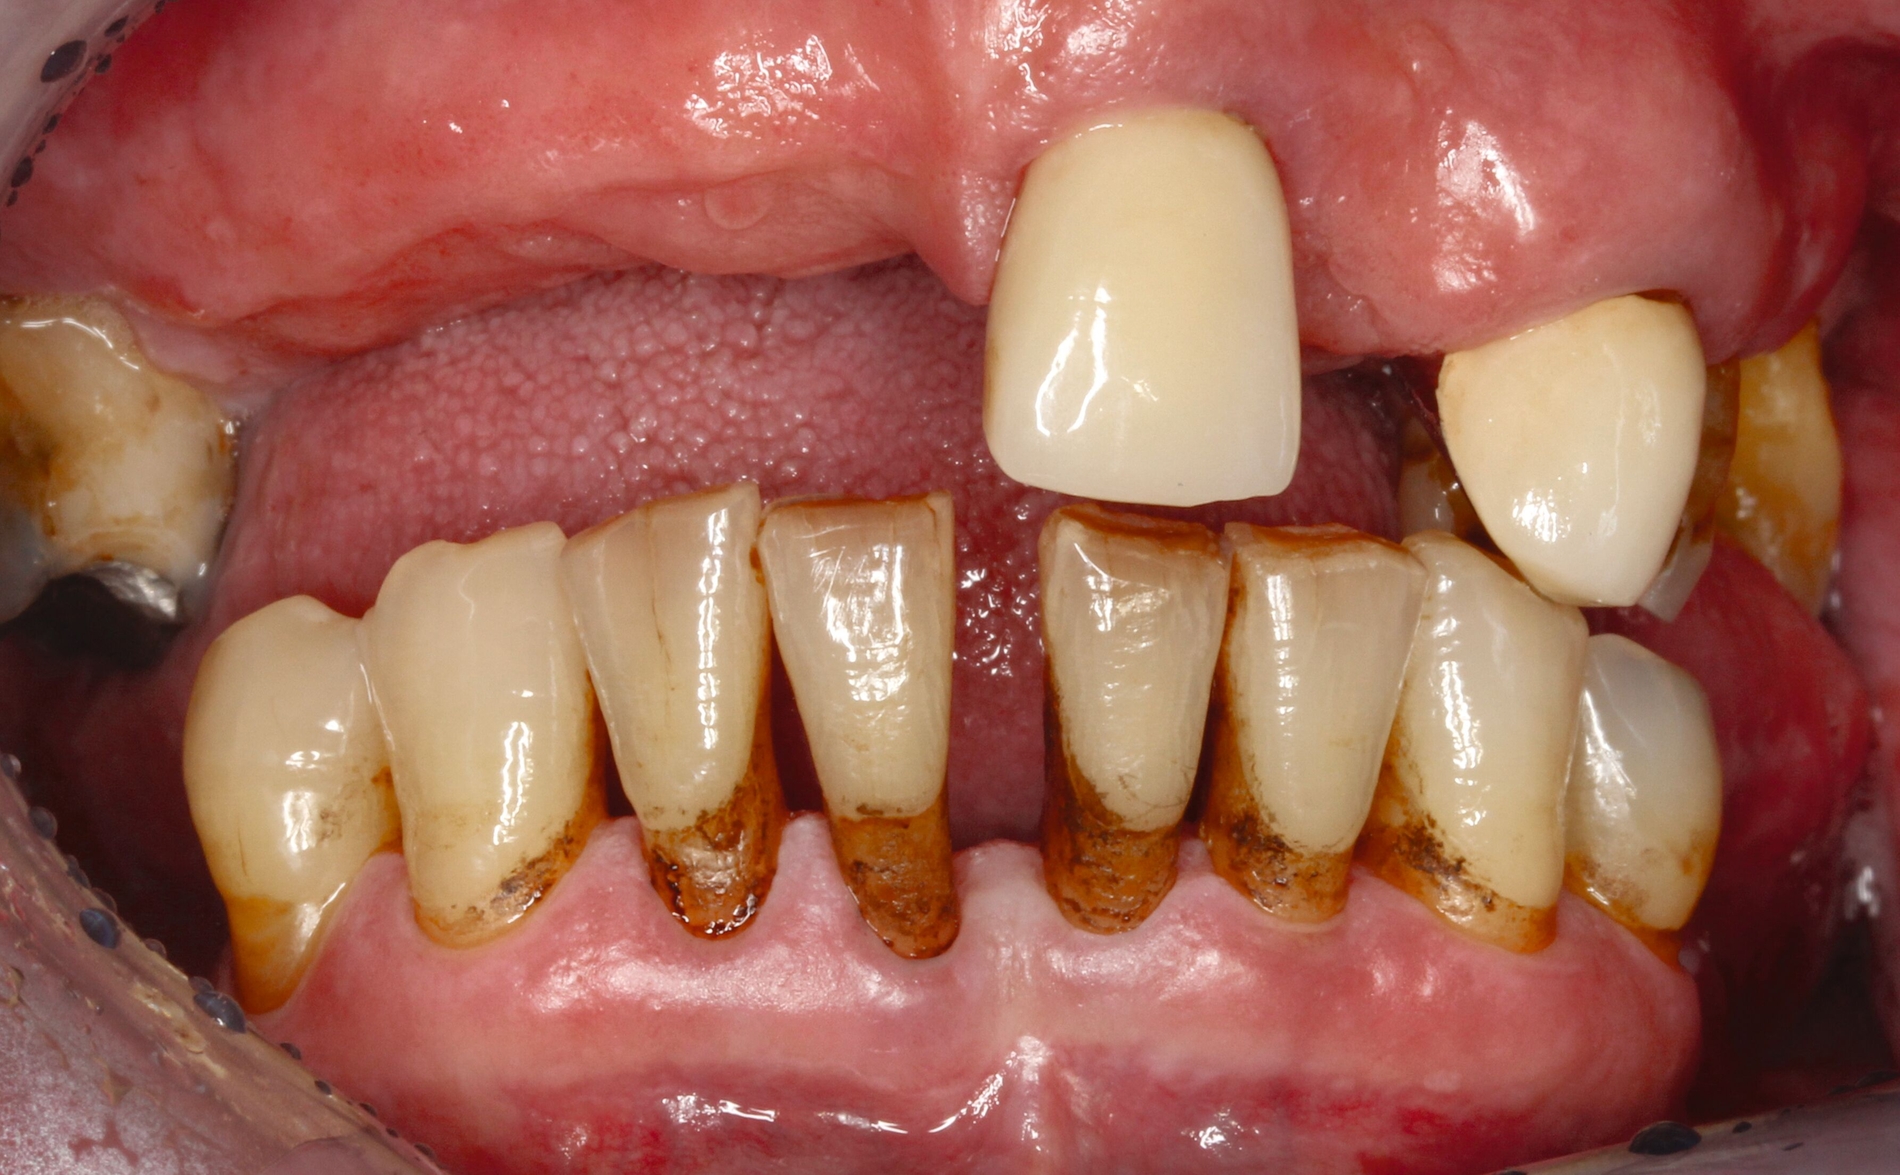

Ist die Läsion aktiv oder inaktiv? Die Beantwortung dieser Frage ist die Ausgangsbedingung für den Therapieentscheid. Wenngleich die Unterscheidung nicht immer einfach ist, ist eine weiche Textur bei Sondieren und eine deutliche Plaquebedeckung ein sicheres Zeichen für Kariesaktivität [Carvalho und Lussi, 2017]. Bei aktiven Läsionen sollten Lokalisation und Ausdehnung genau exploriert werden, was die Behandlungsoptionen wesentlich bestimmt (Abbildung 1). Bei inaktiven Läsionen ist keine restaurative Therapie erforderlich, jedoch sind risikoadaptierte Präventionsmaßnahmen angezeigt.

Eine bekannte Nebenwirkung bei Anwendung auf kariösen Läsionen ist die Schwarzfärbung des behandelten Bereichs (Abbildungen 3, 4). Verfärbungen können aber auch bei Applikation auf kariesfreien Wurzeloberflächen entstehen, diese sind jedoch mit einer professionellen Zahnreinigung gut zu entfernen (Abbildung 2).